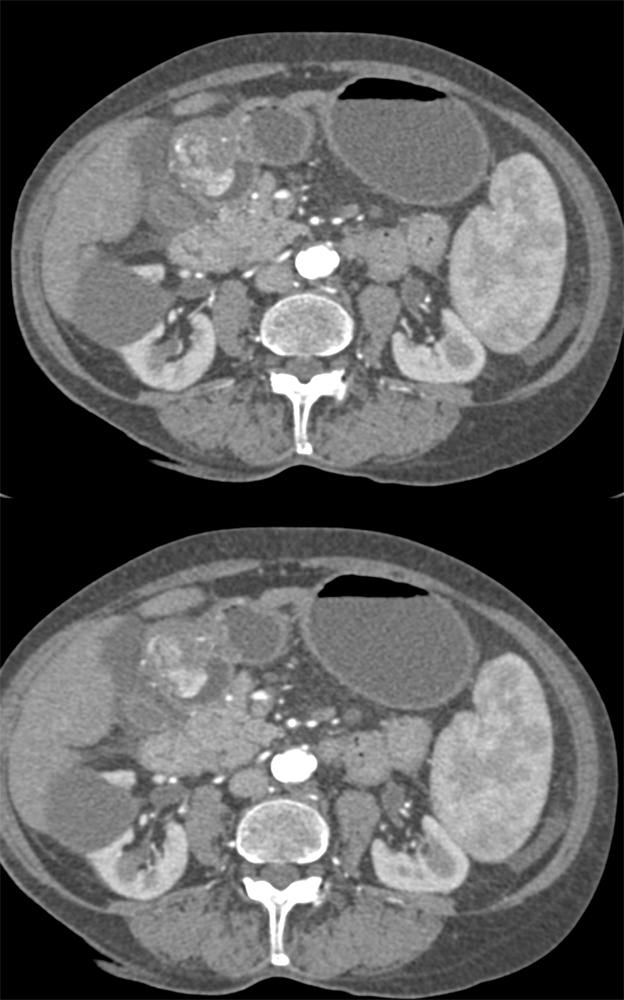

Watermelon stomach (WMS), or gastric antral vascular ectasia (GAVE) ![]() |

“In our patient, the findings of prominent mucosal folds extending from the pylonic channel on upper gastrointestinal series and the thickened antral wall on CT scans correlate well with the known pathologic appearance of gastnic antral vascular ectasia. Histologically, antral thickening results from a combination of foveolar and fibromuscular hyperplasia. Grossly, the antral fold prominence appears to result from bunching of the mucosa in the thickened, hypercontractile antrum.” Gastric antral vascular ectasia ("watermelon stomach"): radiologic findings. Urban BA, Jones B, Fishman EK, Kern SE, Ravich WJ. Radiology. 1991 Feb;178(2):517-8. |

“Gastric antral vascular ectasia primanily affects women (9:1 female-to-male ratio) aged 56-76 years, and is associated with liver cirrhosis (37%) and achlorhydnia (35%). The usual symptoms are iron-deficiency anemia and melena due to chronic gastrointestinal bleeding from the dilated, superficial, and easily traumatized vessels. Antrectomy is curative, but endoscopic treatment with heat probes or lasers has shown promise.” Gastric antral vascular ectasia ("watermelon stomach"): radiologic findings. Urban BA, Jones B, Fishman EK, Kern SE, Ravich WJ. Radiology. 1991 Feb;178(2):517-8. |